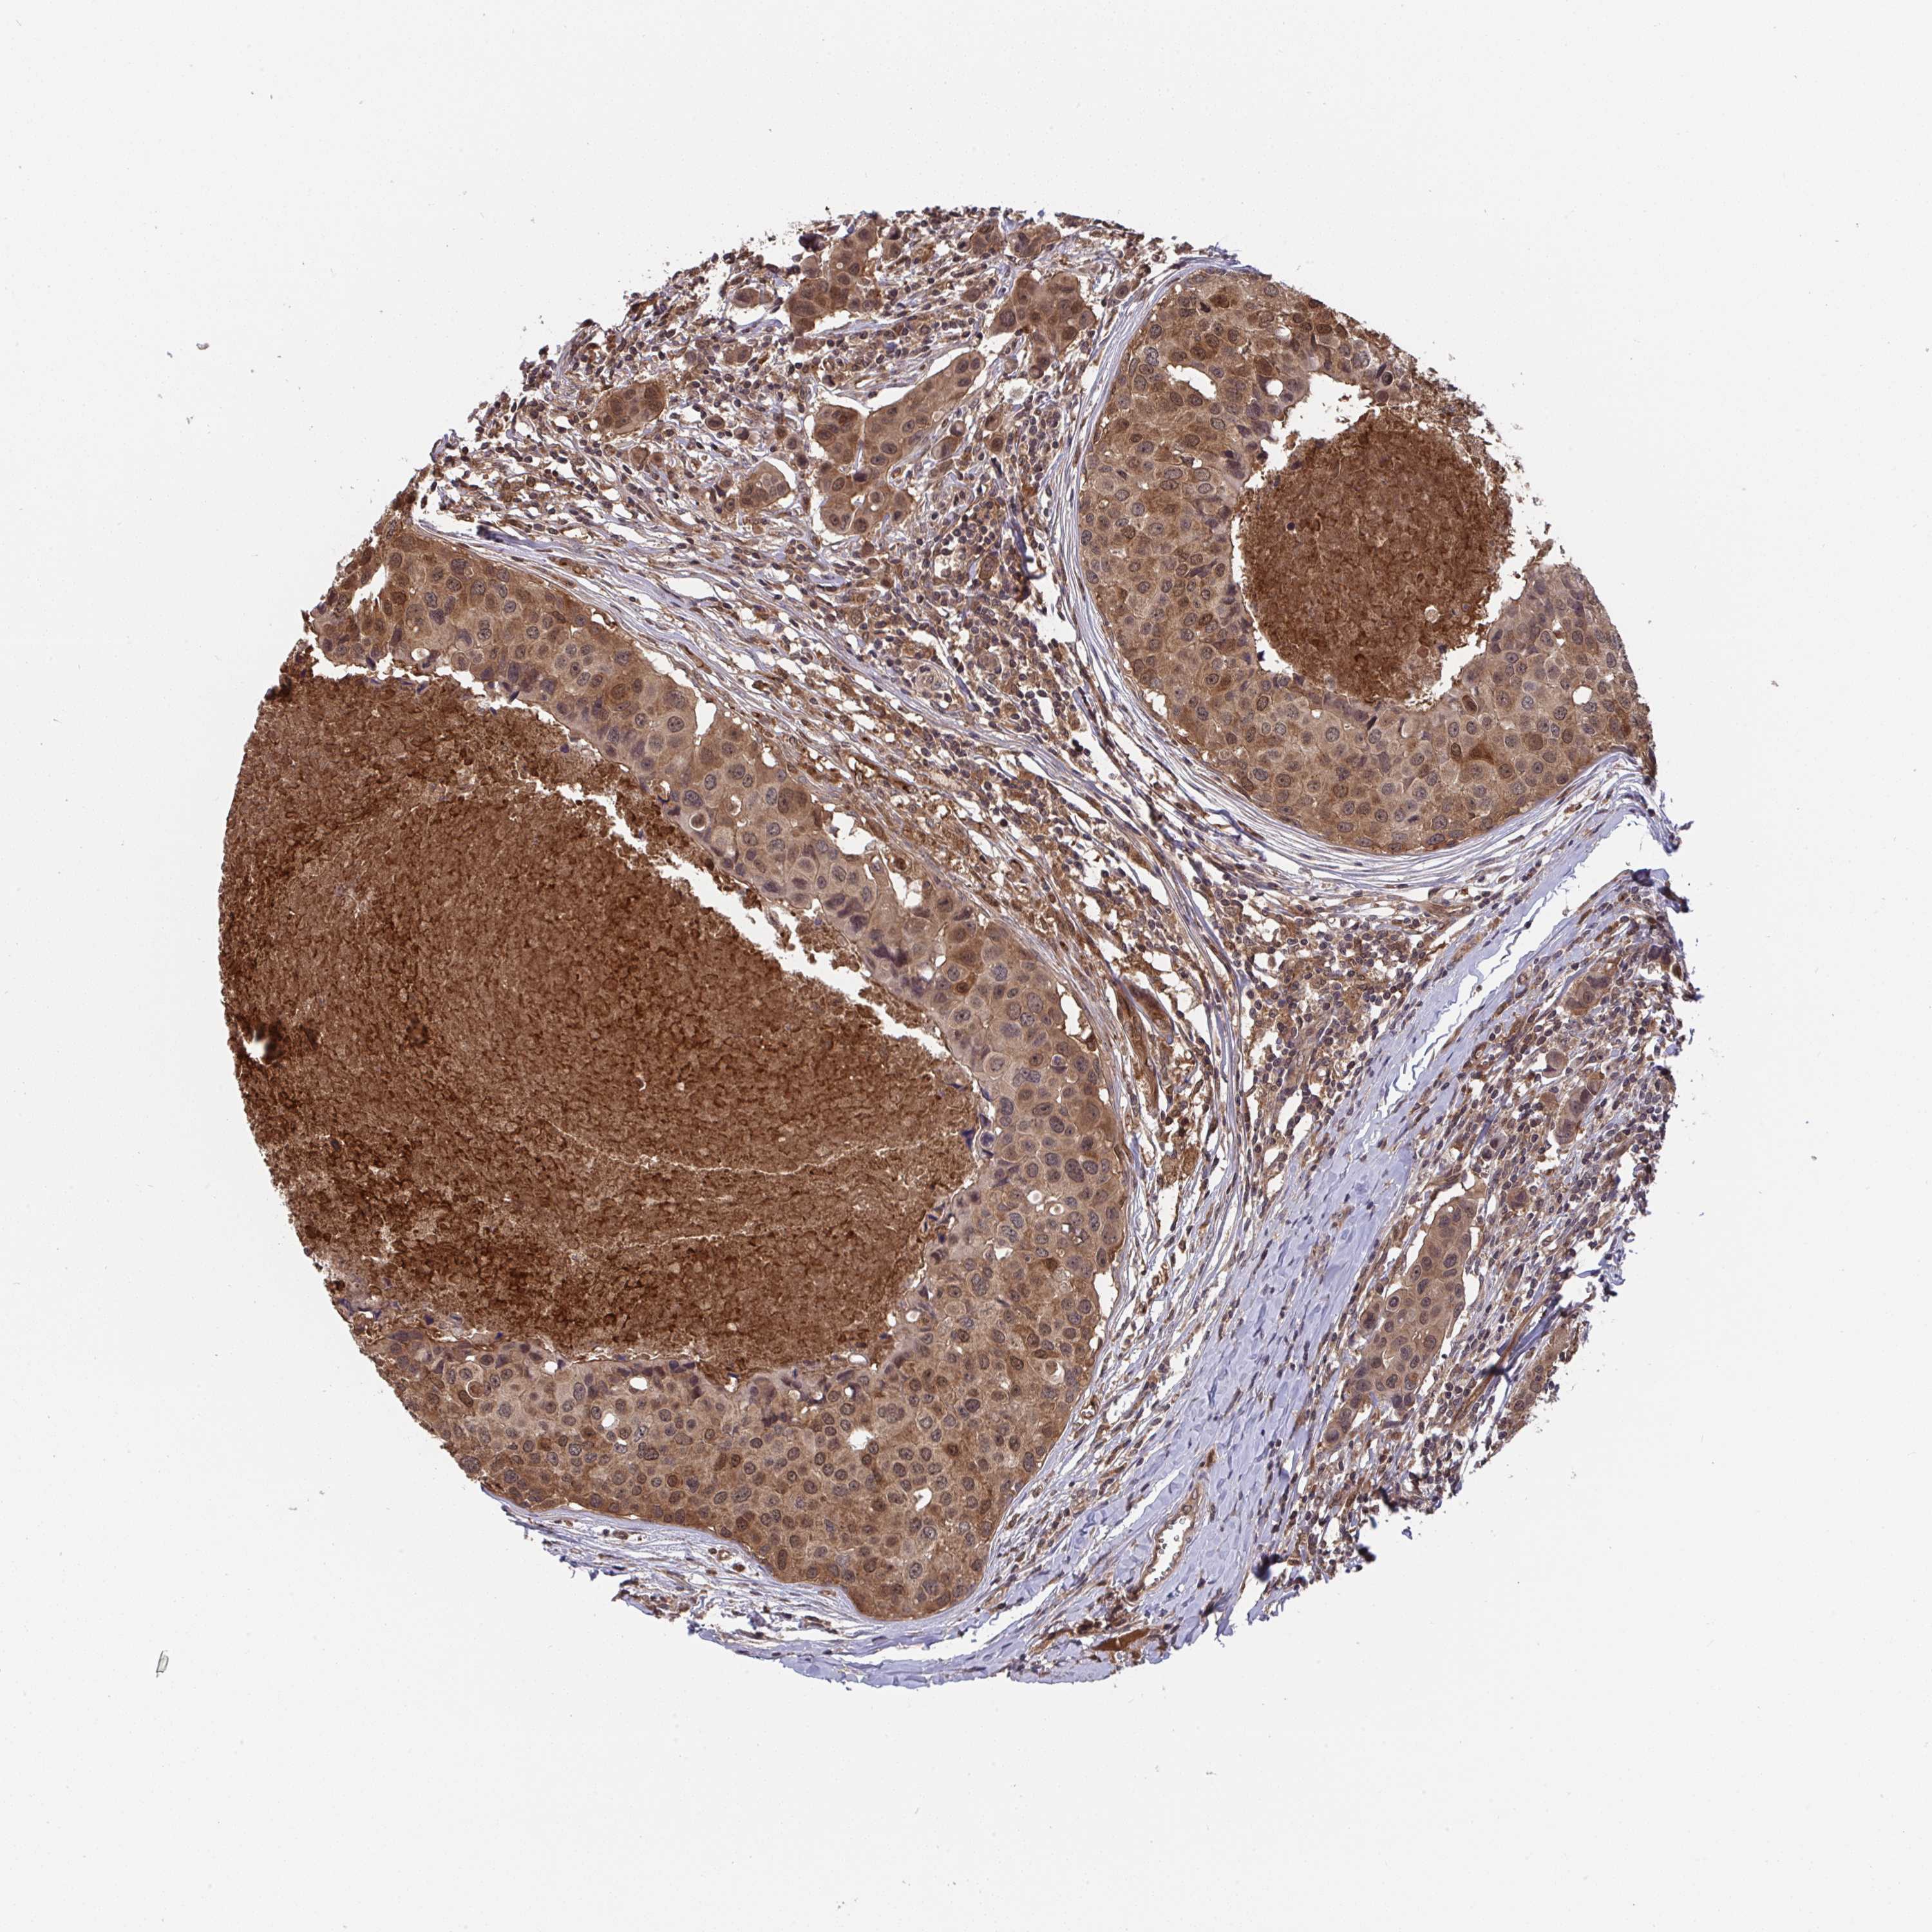

CANCER BREAST CANCER Show tissue menu

BRCA TCGA BRCA VALIDATION PROTEIN EXPRESSION